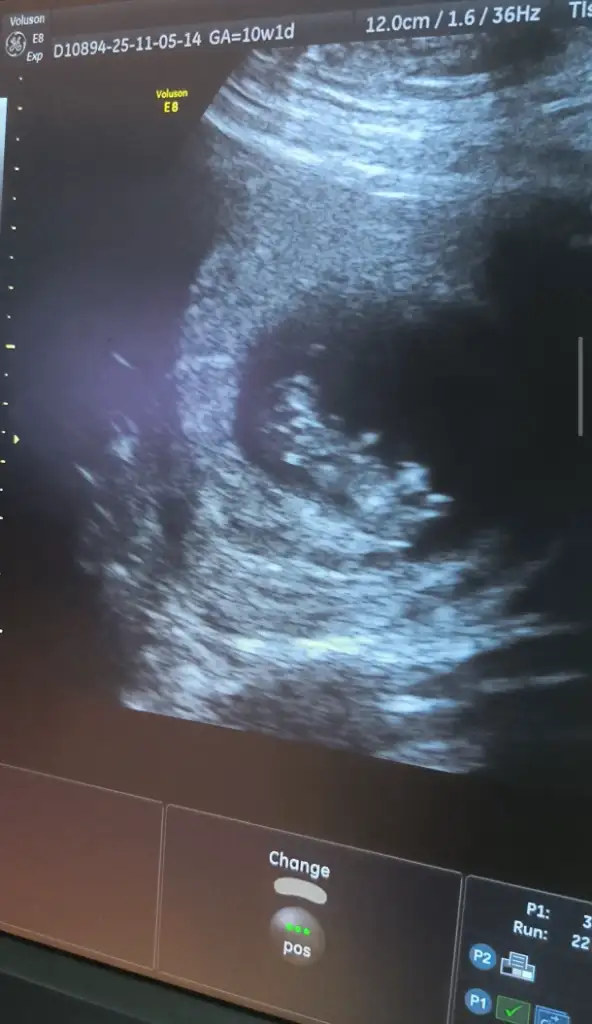

Valla bugün gittim gördüm açıkçası ben üniversite hastanesine gidip fetal DNA için birazda bilgi almak istedim. Fetal DNA yaptiricam. O yüzden gittim kan tahlilleri falan kontrolünude yaptırdım. Fetal DNA sonucum çıktığında tekrar giderim diye düşündüm.

Şu an böyle danslar yapıyor kendince teyzeleri 🥹